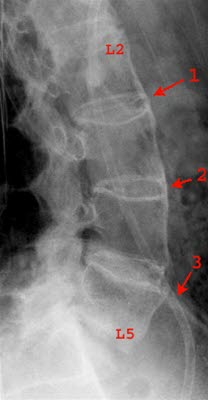

Røntgen, CT- og MR-undersøkelser

Røntgenundersøkelse av ryggsøylen kan vise karakteristiske skjelettforandringer i korsryggen. De typiske funnene ses i overgangen mellom lendevirvlene og bekkenknoklene, i iliosakralleddene (IS-leddene) og i rommet mellom lendevirvlene.

Ofte må sykdommen ha pågått lenge før skjelettforandringene blir synlige ved vanlig røntgenundersøkelse. I tidlig fase kan det derfor være aktuelt å foreta mer avanserte bildeundersøkelser, for eksempel CT (computer tomografi) eller MR som kan påvise forandringene tidligere.

I tidlig sykdomsfase forventes ikke funn på røntgen slik at praksis ofte blir at man tar både MR- og røntgen av IS-ledd. Dersom MR ikke kan gjøres, er CT av IS-leddene et alternativ.